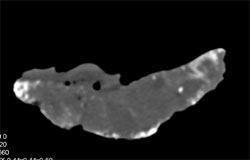

Fetus on the Run